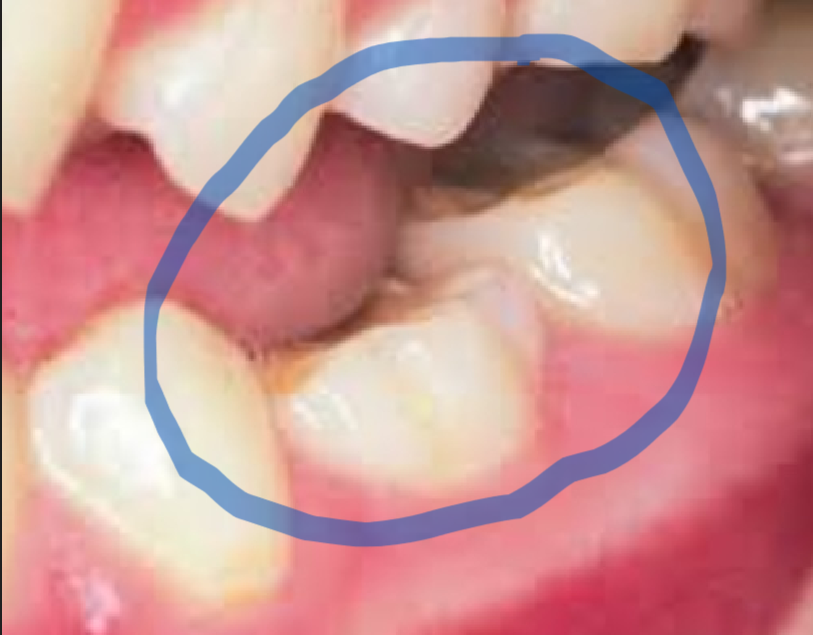

På billedet kan man se eks. af en ankyloserede tand, som sidder lavere end de andre. Det skyldes den stærke forbindelse mellem tanden og kæbeknoglen.

Ankyloserede tænder – er tænder, som er mere forbundet og sidder generelt meget mere fast på kæbeknoglen.

Nå man banker med sit værktøj på de ankyloserede tænder, kan man tydeligt høre en helt hul og forbundet lyd med resten af kæben.